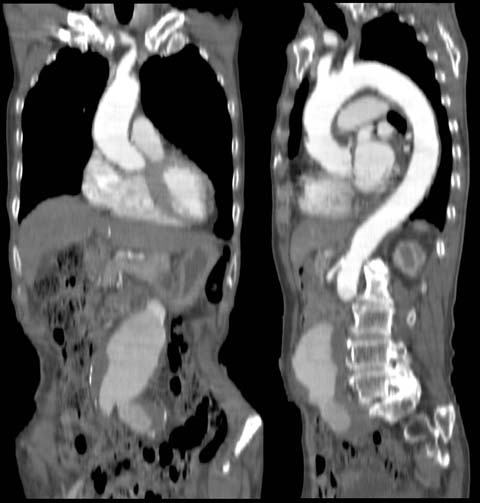

MPR

Data acquired & processed by H. Anno M.D.